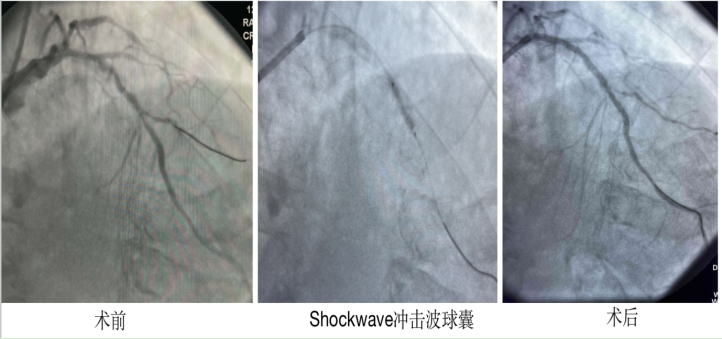

67岁的陈某,患糖尿病15年,近半年来反复胸痛,检查显示冠状动脉病变严重,前降支、回旋支及右冠三支病变,特别是前降支近中段弥漫性狭窄伴重度钙化。

为了能顺利完成血运重建治疗,尽快缓解患者痛苦,心病科组织骨干力量对患者病情进行充分术前评估讨论。在导管室无冠状动脉高频旋磨及激光斑块消蚀术相关设备情况下,团队决定使用国际最新技术“Shockwave冲击波球囊”对患者进行治疗。

术中“Shockwave冲击波球囊在延长导管辅助下到位,工作压力4atm,释放脉冲。”进行了8个周期的治疗,球囊导管逐渐膨胀充盈,再次经过切割球囊和高压球囊的“修饰”。复查造影显示:病变狭窄明显缓解,管腔面积得到有效恢复,血流通畅,随后为患者植入两枚药物球囊,术后患者安返病房,胸痛症状消失,目前已康复出院。